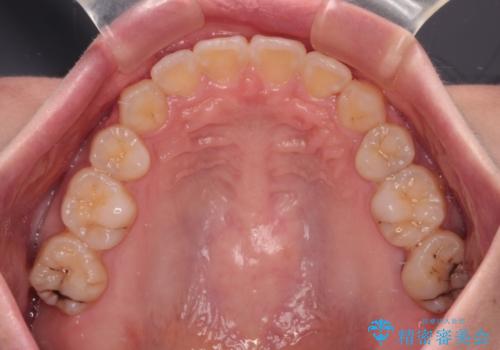

- 前歯のデコボコや口元の突出感、口の閉じにくさを気にして来院された患者様です。

上下左右第一小臼歯4本を抜歯し、ワイヤー装置にてデコボコを解消しながら口元を引っ込めるよう矯正治療を行うこととしました。

抜歯スペースを閉じている過程で、左側の上下犬歯が引っかかってしまい、進捗が停滞しましたが、当初予定の2年~2年半の間で無事に治療を終えることができました。